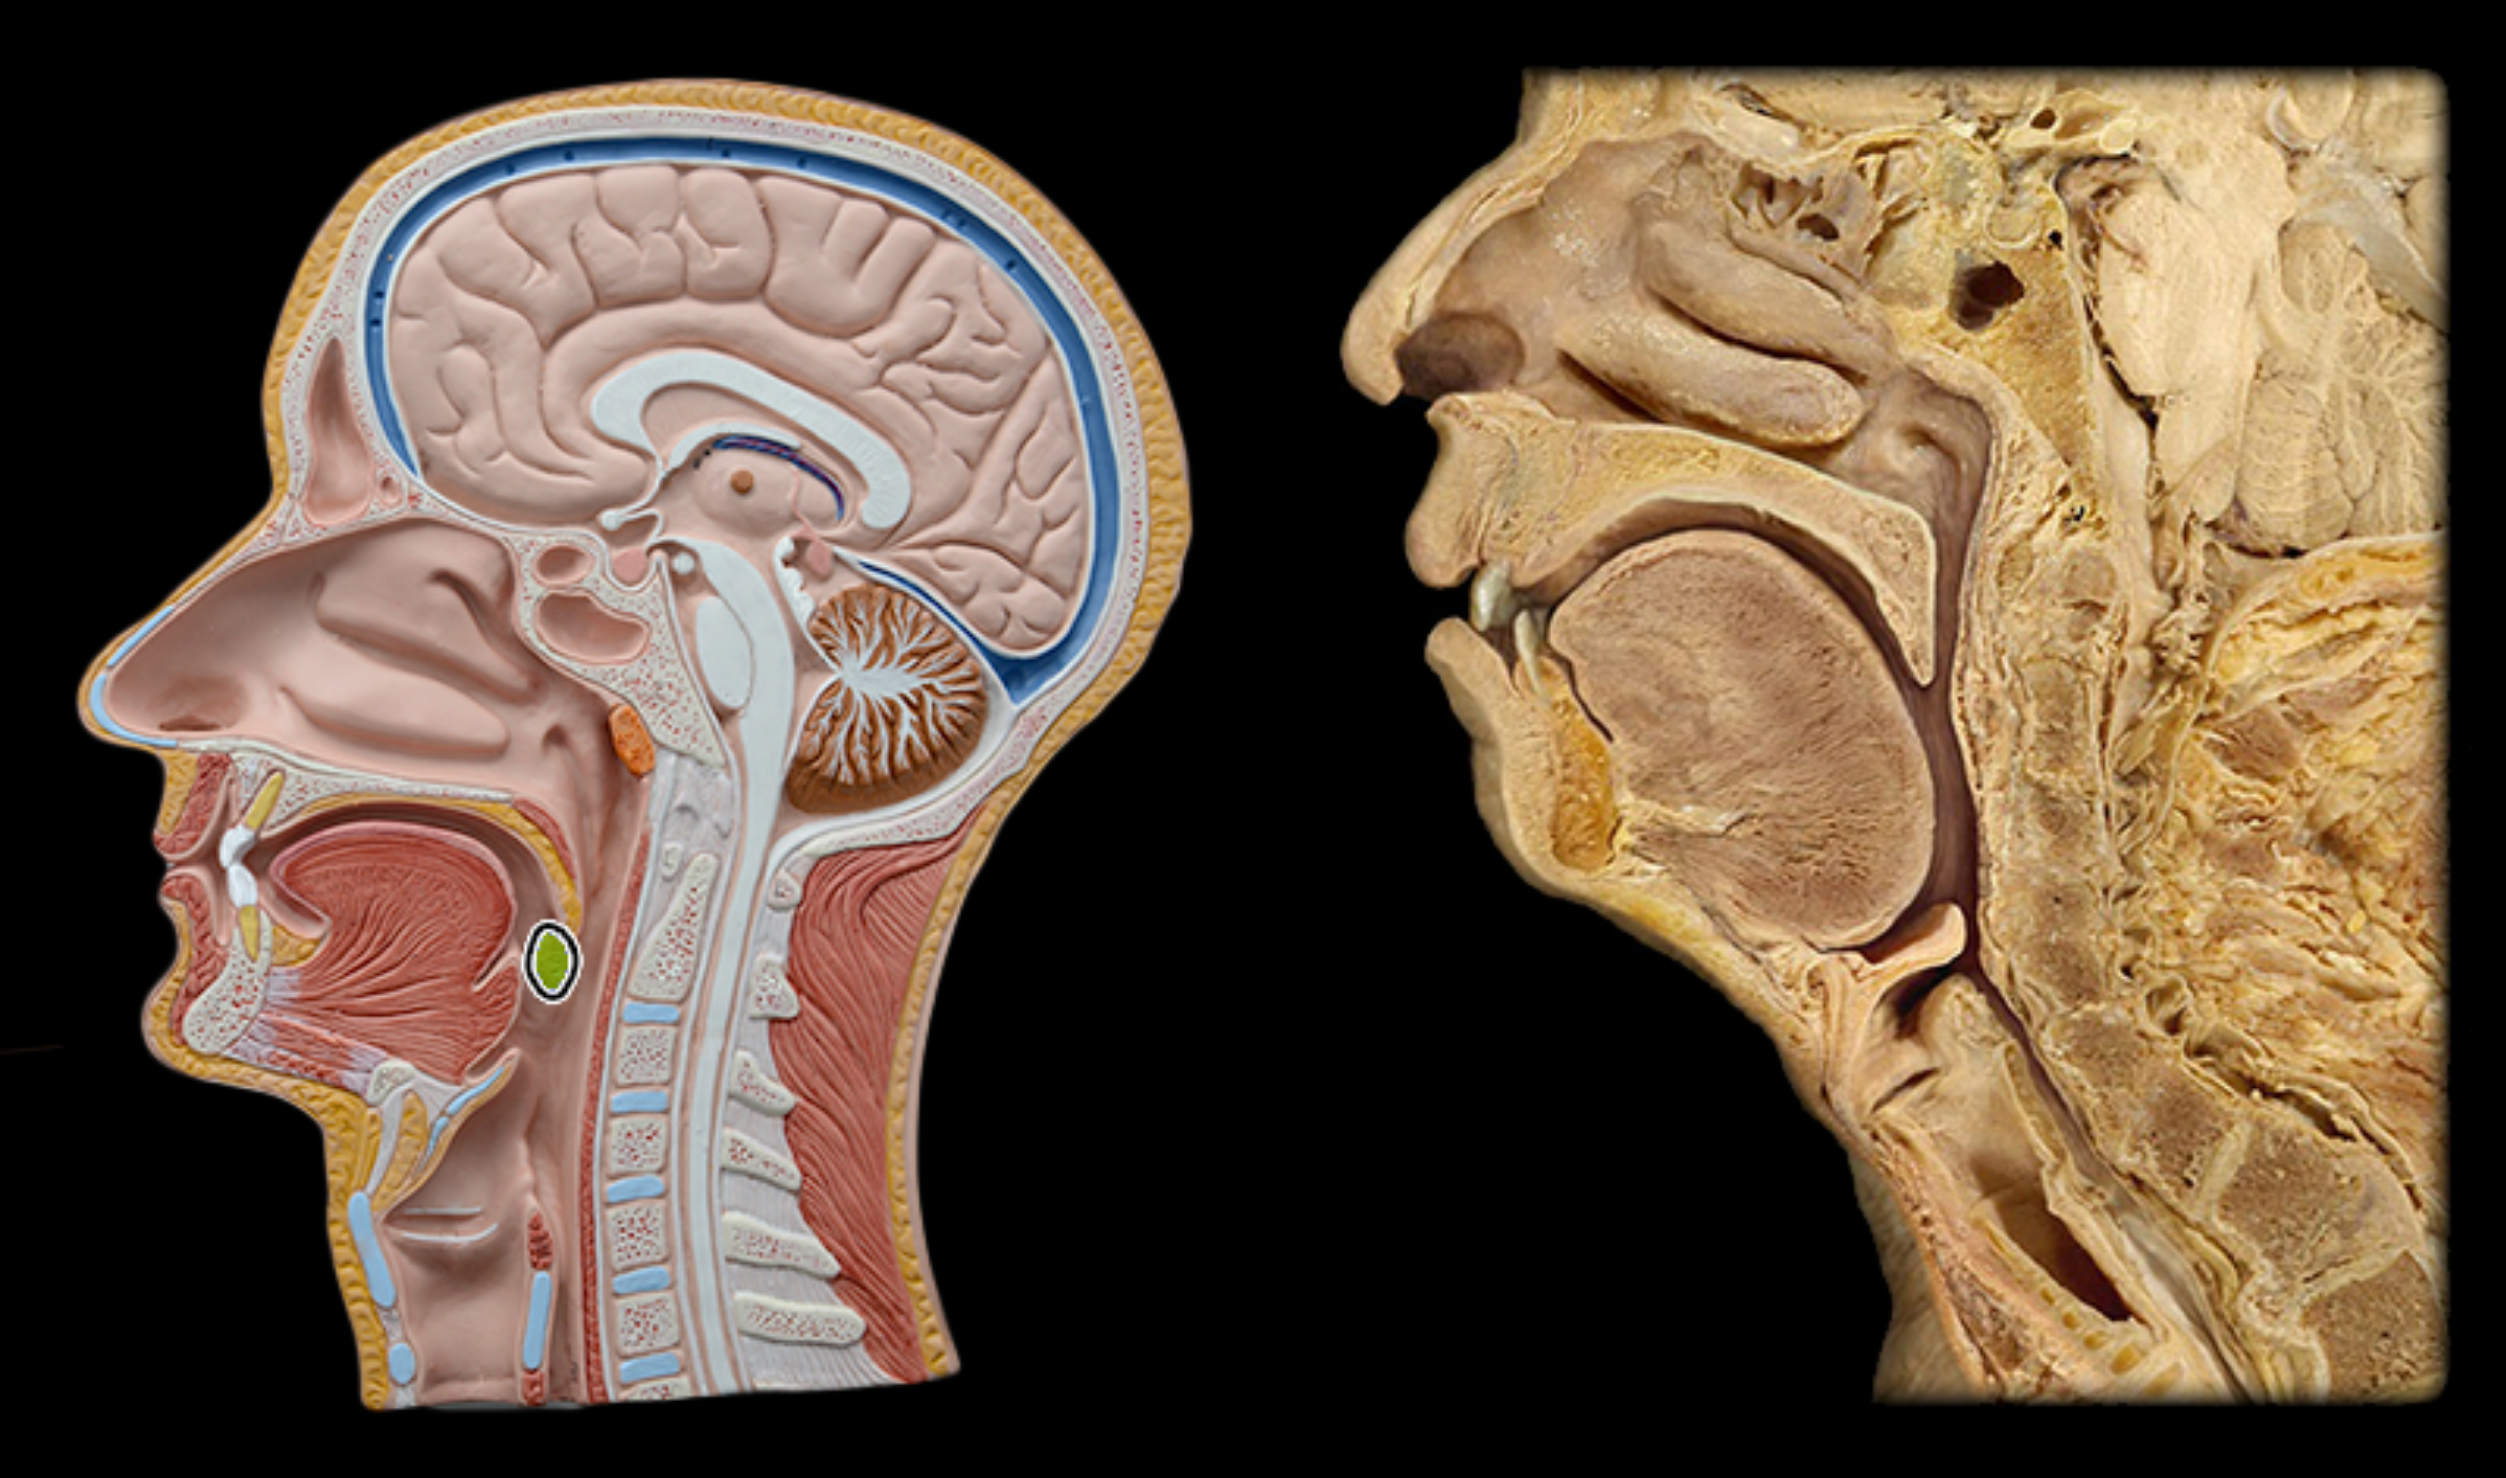

Pharyngeal tonsil

Lingual tonsil

Palatine tonsil